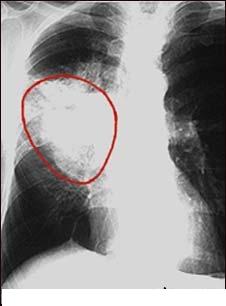

Fumatul produce cancer pulmonar